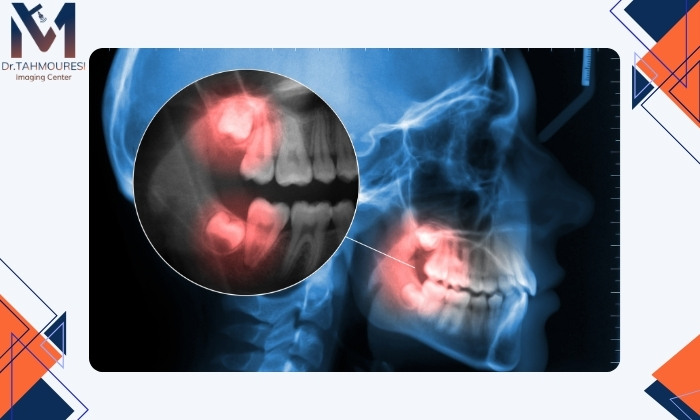

اگر دندان کناری دچار پوسیدگی شده باشد معمولاً تمیز نکردن ناحیه بهدلیل موقعیت این دندان عامل آن است و جراحی توصیه میشود.رشد کج، افقی یا نیمهنهفته دندان عقل

وقتی دندان عقل بهصورت کج یا افقی رشد میکند یا فقط بخشی از آن بیرون میزند بهطور طبیعی نمیتواند اصلاح شود و اغلب باید جراحی شود.درد فک یا سردردهای مکرر بدون علت مشخص